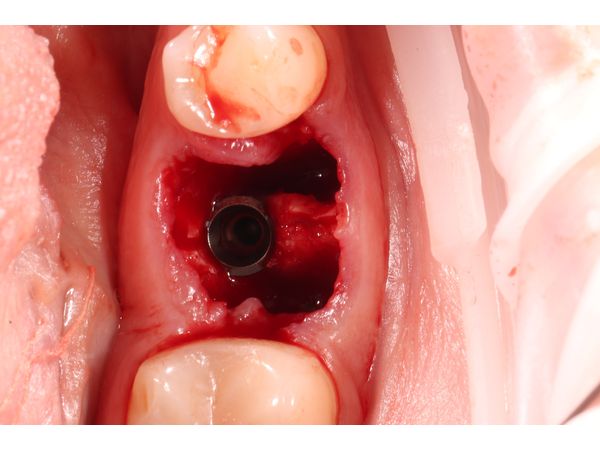

- установили дентальный имплант размером 4,3×10 мм фирмы SNUCONE в межкорневую перегородку;

- заполнили лунки корней биотропным ксенографтом (остеопластическим материалом).